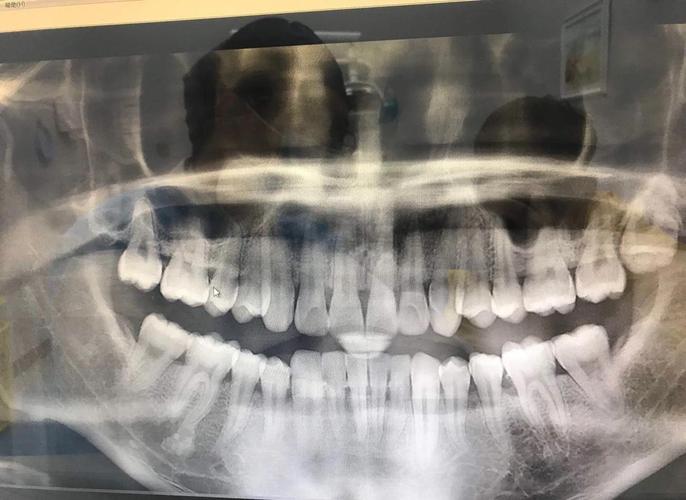

智齿(第三磨牙)通常在17-25岁萌发,这一年龄段恰好与牙齿矫正的高峰期重叠,正畸治疗一般需要1-3年,期间患者年龄可能正处于智齿萌发活跃期,矫正中长智齿”并不罕见,智齿的萌发状态多样:有的完全埋伏在颌骨内,有的部分萌出(仅露出牙冠),有的则已完全萌出但位置不正(如倾斜、近中阻生等),临床数据显示,约60%-70%的成年智齿存在不同程度的萌出异常,而正畸患者中因智齿问题需额外干预的比例约15%-20%。

少数情况下,异常萌出的智齿牙根可能与矫正牙齿的牙根距离过近,长期压迫可能导致相邻牙根吸收(牙根变短),影响牙齿的长期稳定性,这种情况较为罕见,通常需通过X光片才能发现。

医生通常会通过曲面断层片或CBCT(锥形束CT)评估智齿的位置、萌出方向、与邻牙及牙根的关系,判断是否需要干预。

若智齿完全萌出、位置正(与对颌牙正常咬合)、无邻牙压迫、且患者口腔清洁到位,一般无需拔除,仅需在矫正期间定期观察(每6个月拍一次X光片)。